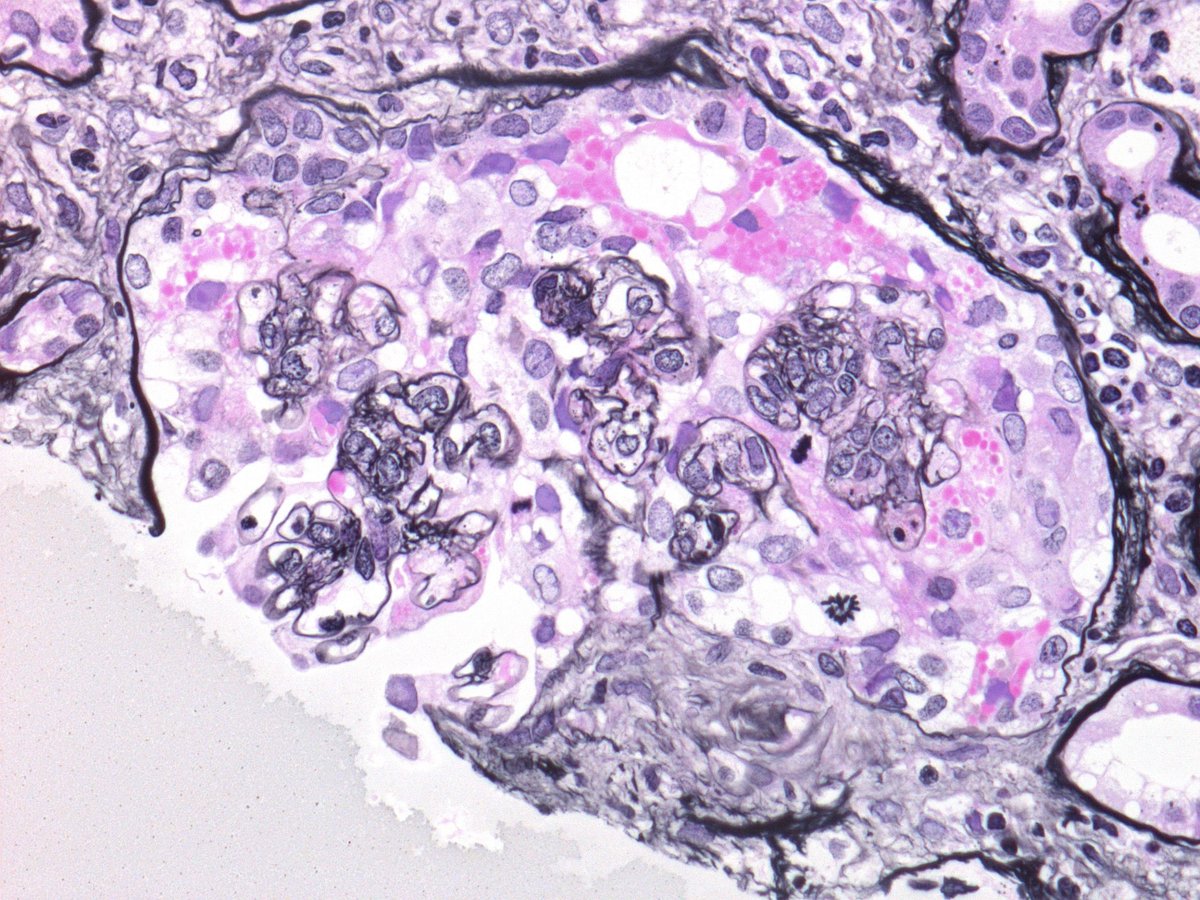

Seen in a case of IgAN. Do you think this represents collapsing glomerulopathy or a cellular crescent? How many mitotic figures do you see?